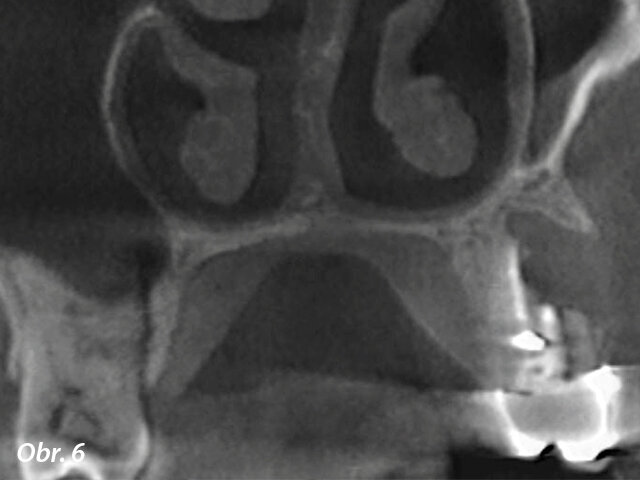

U horního premoláru na obr. 5, 6 odhalil fistulogram přítomnost apikální léze, která zasahovala koronálním směrem asi do střední třetiny kořene. Rozhodování o klinickém postupu tedy mohlo vést k ortográdní revizi endodontického ošetření. CBCT nám ale poskytlo zcela jiný pohled na situaci v porovnání s intraorálním snímkem, ukázalo totiž, že byl zub při předchozím ošetření nevratně poškozen a musí být extrahován.